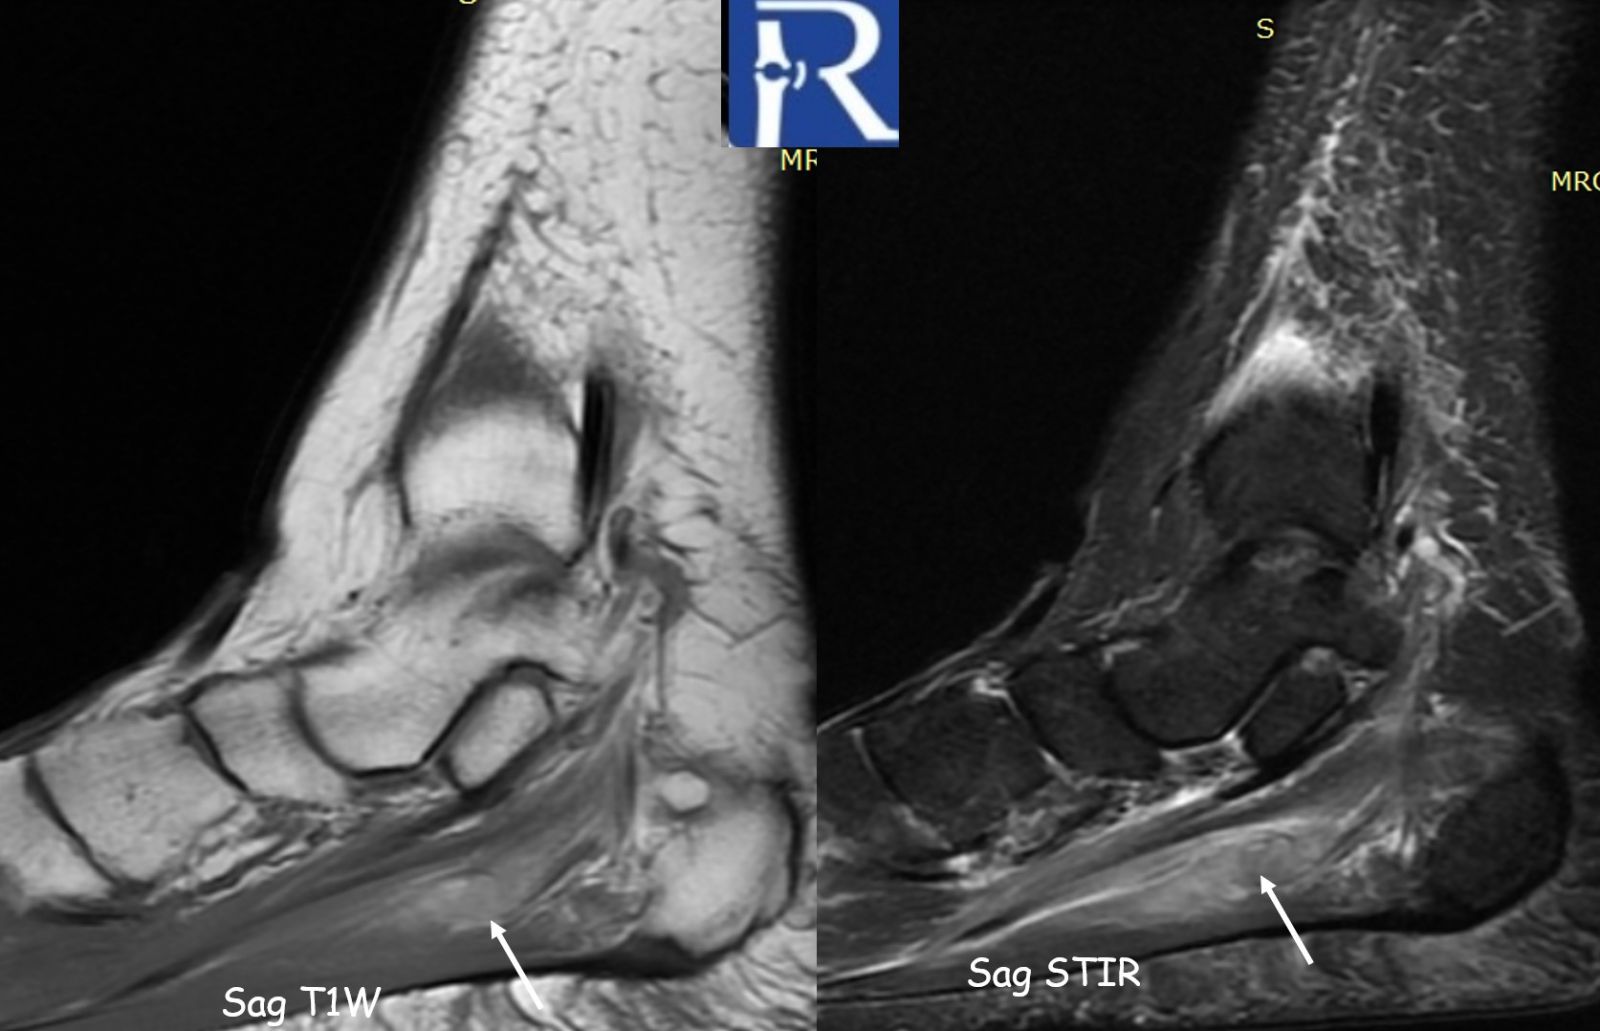

MRI of the left ankle demonstrated:

- Loss of normal venous flow void in the lateral plantar vein

- Venous dilatation

- T1 hyperintense intraluminal signal compatible with subacute thrombus

- Hyperintense thrombus on proton density fat-suppressed sequences

- Prominent perivascular soft tissue edema extending into adjacent musculature

Perivascular edema was the most conspicuous indirect sign.

MRI findings described in the literature include:

- Loss of normal venous flow void

- Venous enlargement

- Intraluminal signal abnormality depending on thrombus age

- Perivascular edema

Perivascular edema, in particular, may serve as an important indirect imaging clue prompting focused vascular assessment.